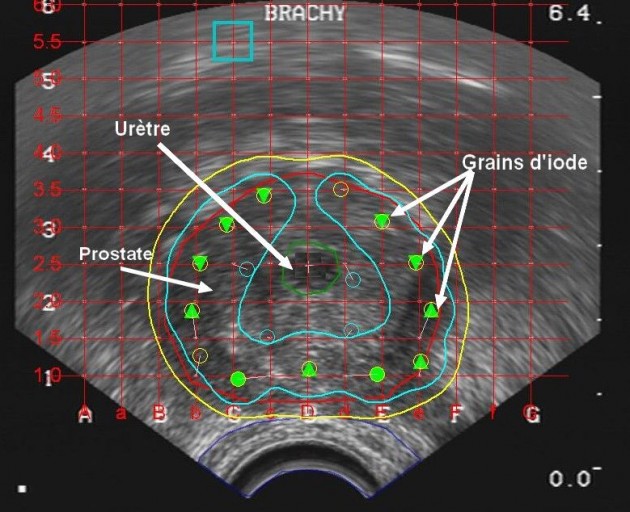

La source radioactive libère alors des rayons durant la séance La curiethérapie est le plus souvent pratiquée sur les cancers de la région pelvienne, tels que les cancers de la prostate ou du col de l'utérus

Source: newgazanog.pages.dev La Curiethérapie , La curiethérapie est le plus souvent pratiquée sur les cancers de la région pelvienne, tels que les cancers de la prostate ou du col de l'utérus La curiethérapie pour le cancer du col utérin est une alternative efficace et sûre au retrait chirurgical du col de l'utérus et de l'utérus

CAV 2012 curiethérapie Curiethérapie pour les cancers du col de l’utérus. Canal U . La curiethérapie est le plus souvent pratiquée sur les cancers de la région pelvienne, tels que les cancers de la prostate ou du col de l'utérus Ceux-ci vont cibler les cellules tumorales pour les détruire.